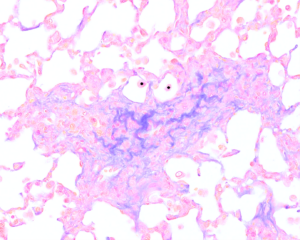

This image was captured as part of a study investigating C-type natriuretic peptide (CNP) as a potential treatment for pulmonary fibrosis. CNP occurs naturally in the body and can prevent scar-forming fibroblasts from multiplying and depositing stiff collagen, the main component of scar tissue. The image shows scarred lung tissue from a mouse in which the gene for CNP was switched off. Without CNP, fibrosis may develop more aggressively.

By studying lung tissue under the microscope, researchers can see how scarring develops when CNP is absent and test whether restoring CNP could protect against pulmonary fibrosis. Understanding how fibrosis spreads at the cellular level gives scientists the knowledge needed to develop new treatments for this challenging disease. Studies like this provide hope that, in the future, we may be able to slow, prevent, or even reverse lung scarring, helping patients breathe more easily and live happier, healthier lives.